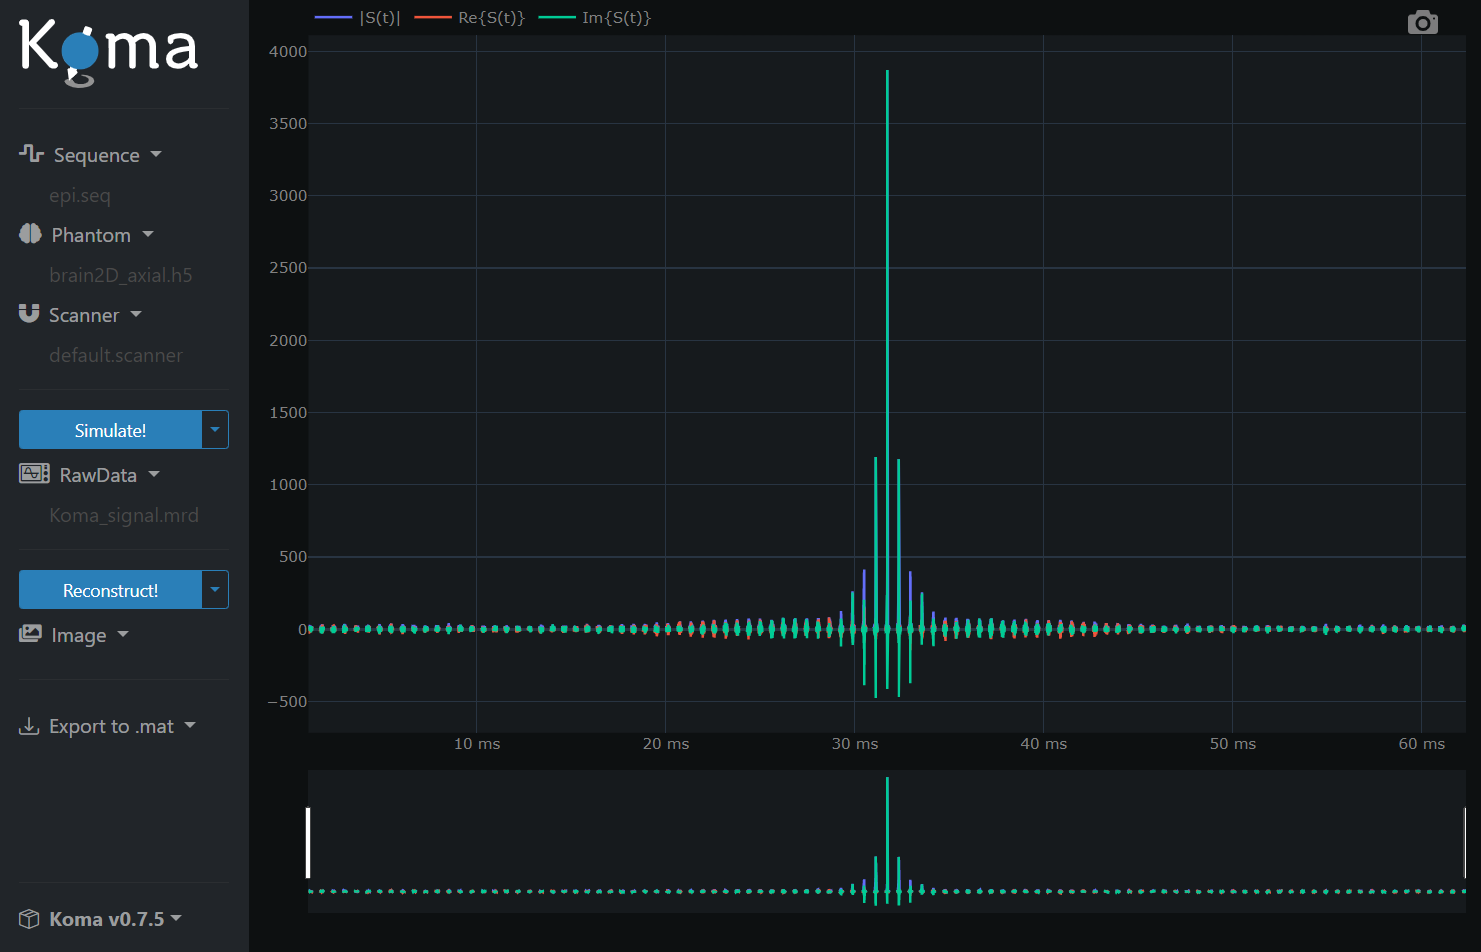

As a simple demonstration, press the Simulate! button and wait until the simulation is ready. Now you have acquired the Raw Signal and you should see the following: